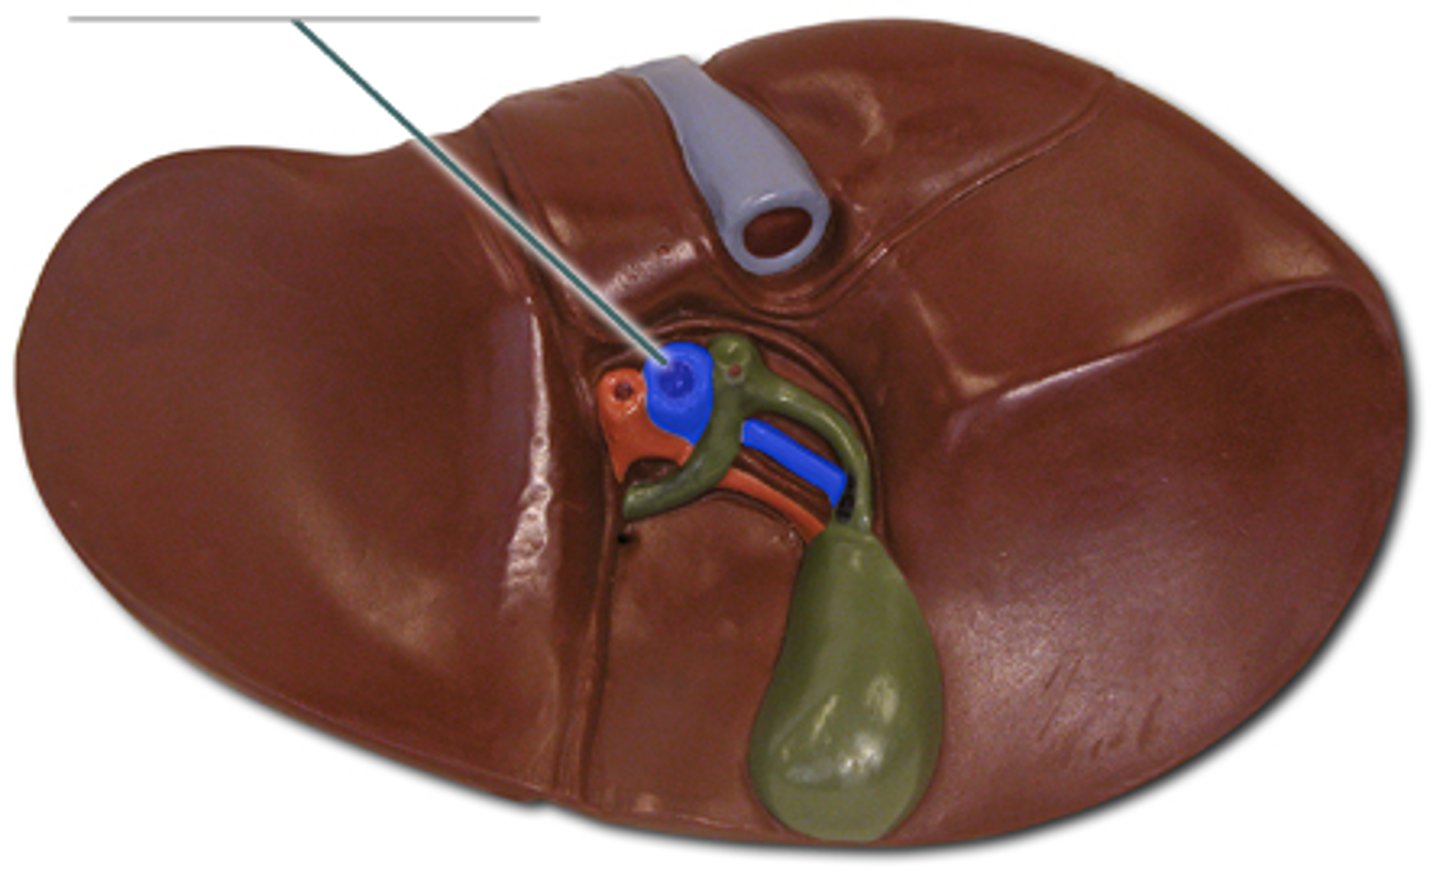

right lobe (of liver)

left lobe (of liver)

quadrate lobe (of liver)

caudate lobe (of liver)

diaphragmatic surface (of liver)

bare area (of liver)

not covered by peritoneum

inferior vena cava

round ligament of liver

porta hepatis

where the blood and lymph vessels, bile ducts, and nerves enter and leave the liver

hepatic artery proper

common bile duct

common hepatic duct

cystic duct

hepatic portal vein

gallbladder

fundus (gallbladder)

body (gallbladder)

neck (gallbladder)